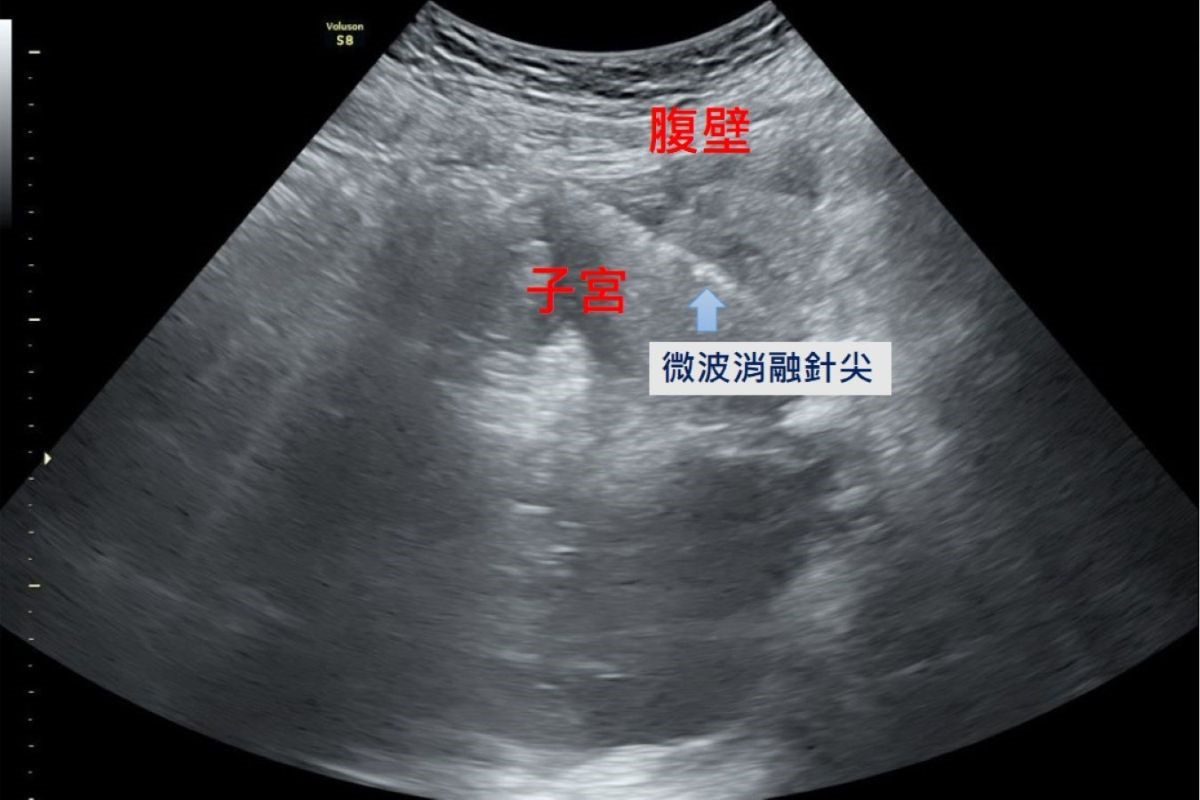

臨床診斷子宮肌腺瘤可以透過病人主訴、內診、超音波及抽血檢查來判斷。過去的治療方式有藥物及手術摘除子宮兩種,藥物治療可暫時控制經痛與經血過多,但長期使用荷爾蒙類藥物抑制劑容易出現類似停經更年期的副作用,例如熱潮紅、盜汗與骨質疏鬆;手術切除全部子宮雖能徹底移除病灶,但對希望保留子宮或仍有生育計畫的女性而言就無法再生育,代價較大;而若只切除局部子宮肌腺瘤,則無法完全清除、症狀改善有限。隨著醫療科技的進步,微波消融成為近年來的治療新選擇,醫師在腹腔鏡及婦科超音波的導引下,將消融針精準進入病灶,釋放高能量微波破壞異常內膜腺體組織,使其失去活性而逐漸縮小壞死,達到止痛與減少經血的治療目的。陳國瑚部長表示:「微波消融治療的範圍可透過影像導引精準掌握,不容易傷害周邊組織,也因為術中保護子宮內膜,病人術後不影響懷孕。此外,微波消融治療術後疼痛感低、併發症風險也較小,根據臨床追蹤,近九成的病人預後狀況良好,能恢復正常月經週期,經痛大為改善,提升生活品質。」

在腹腔鏡及婦科超音波的導引下,將消融針精準進入病灶,釋放高能量微波破壞異常內膜腺體組織,使其失去活性而逐漸縮小。